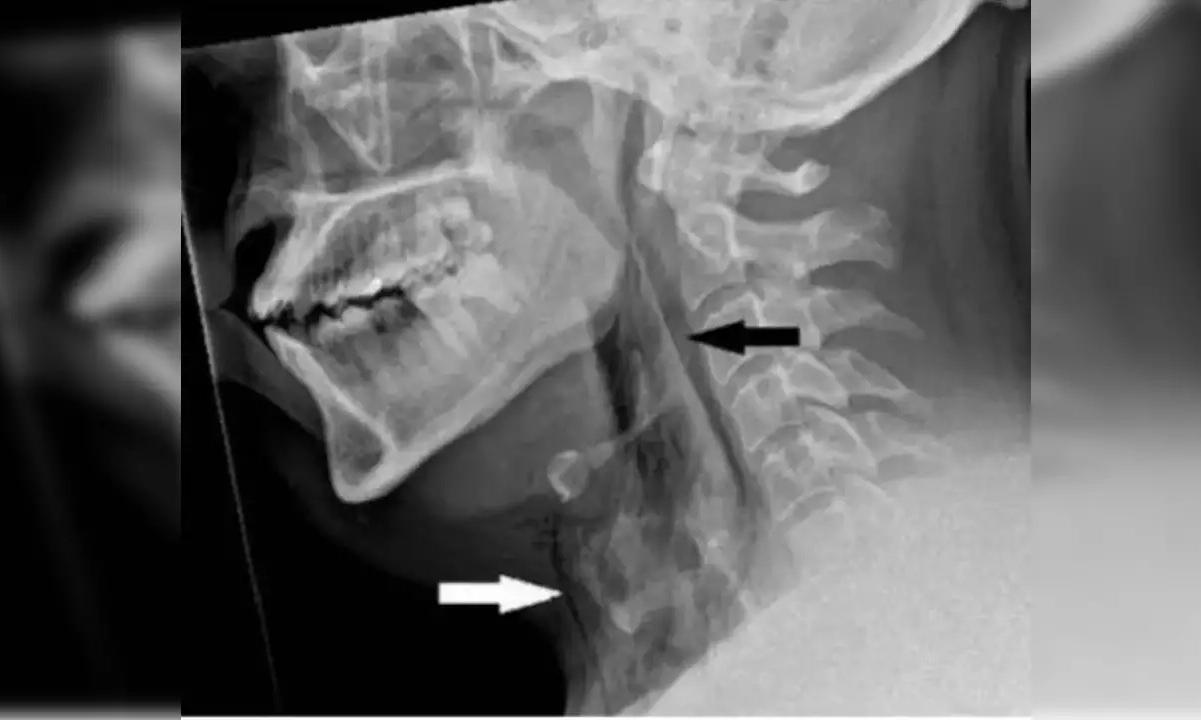

It was revealed by an X-ray that the man had a disease where air becomes trapped behind the skin's deepest tissue layers.

Subsequently, a CT scan showed that the rip was located between his neck's third and fourth vertebrae. Additionally, air had gathered in the area between his lungs and his chest.